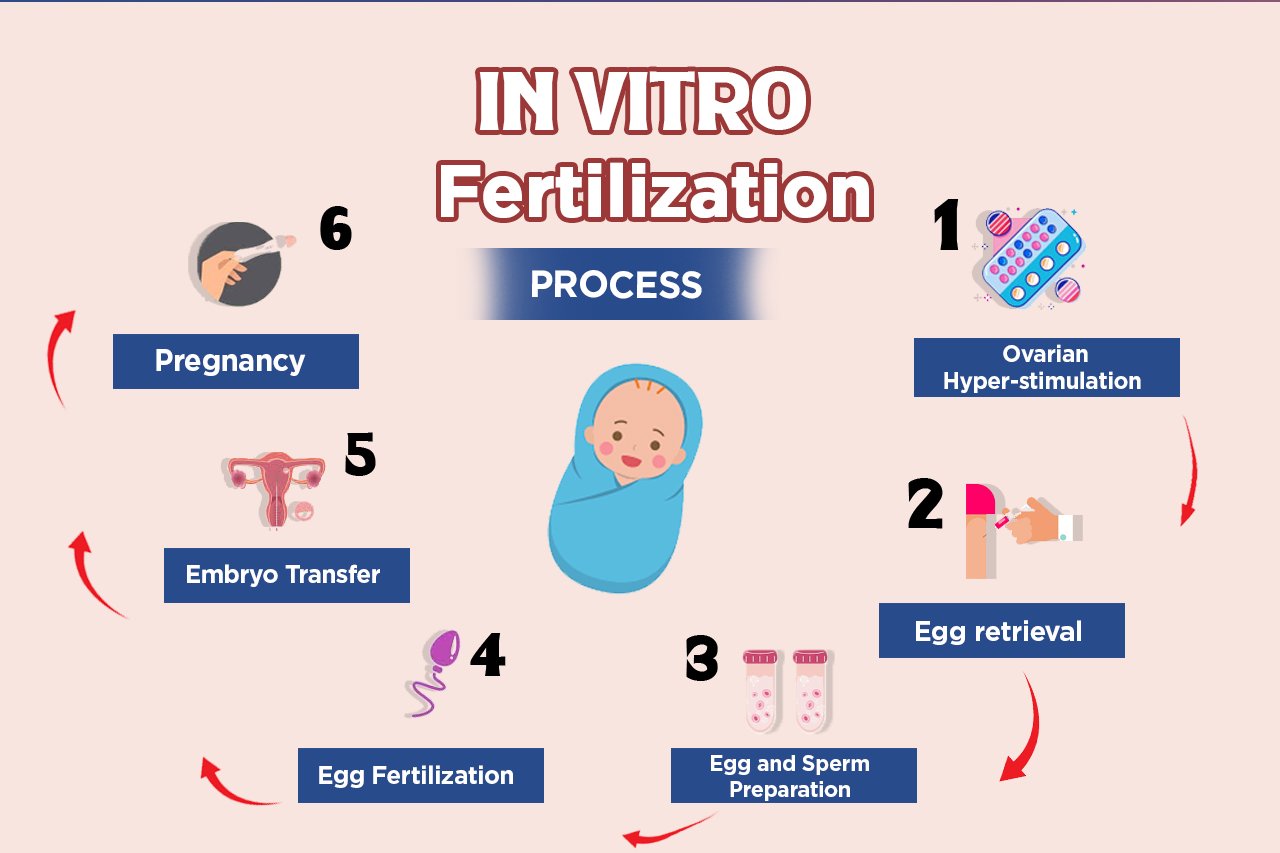

What is IVF and how does it work?

In Vitro Fertilization (IVF) is a fertility treatment where a woman’s eggs are retrieved and fertilized with sperm outside the body, in a laboratory. Once the embryos develop, one or more are transferred into the uterus to establish a pregnancy.

The IVF Process at Wadi Hospital

"At our IVF center, every journey begins with understanding and support. The IVF process is carried out in carefully planned stages, each guided by expert care to give you the best chance at starting or growing your family."